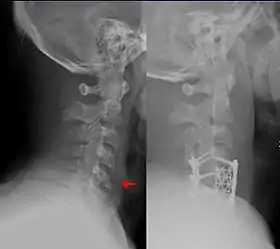

![]() هذا الكسر الموجود بأسفل الفقرات العنقية والمعروف بـ(كسر الدمعة) هو أحد الحالات التي يتم معالجتها من قبل جراحي العظام وجراحي المخ والأعصاب. | |